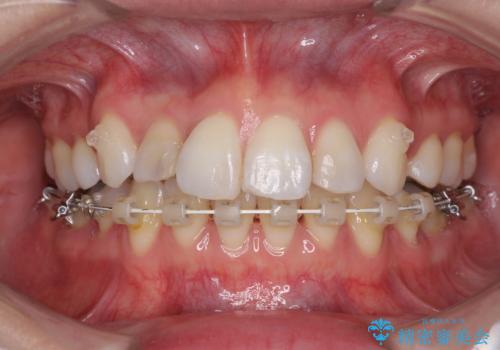

- ハーフリンガル

目立たない装置を希望されたので、上顎が裏側装置のハーフリンガルを選択し、上下左右の小臼歯(計4歯)を抜歯して矯正治療を行うこととしました。

治療期間の目安は3年~3年半でしたが、咬み合わせにより上顎のスペースがなかかな閉じきらず、治療期間が長期化してしまいました。